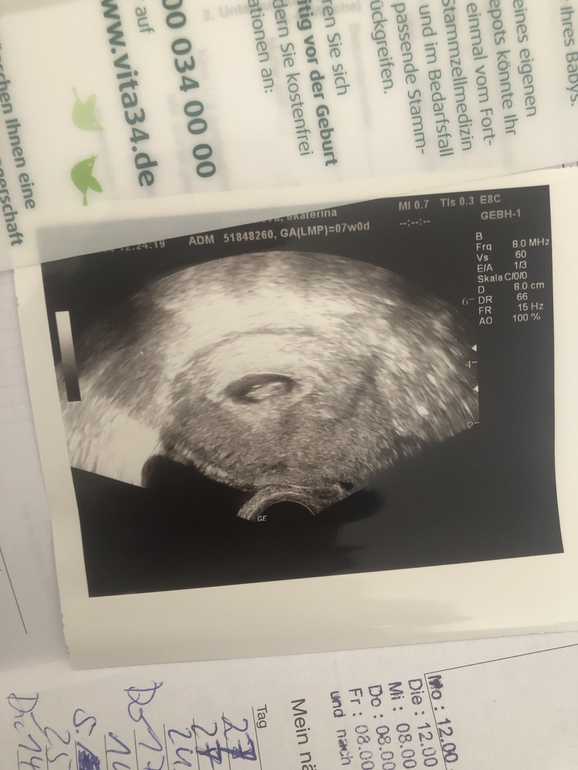

Ekaterina

Надежда умирает последней😁 в Германии пол говорят(предполагают) после 16 недели,не раньше. Долго ждать🤪